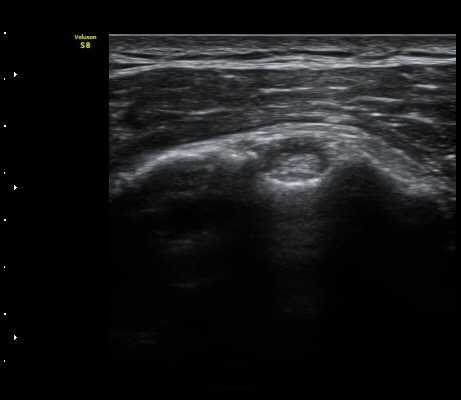

ÀϺΠ±Ø»ó°Ç Á¾´Ü¸é°Ë»ç¿¡¼­ ±Ø»ó°ÇÀÇ ÀüÃþÆÄ¿­°ú ±Ø»ó°Ç¸¦ ¿¬°áÇÑ ºÀÇջ簡 ±¸ºÒ±¸ºÒ(tortous)ÇϰÔ

°üÂûµÇ¾î ºÀÇÕ»ç ÆÄ¿­À» ½Ã»çÇÑ´Ù(»çÁø 5, 6).